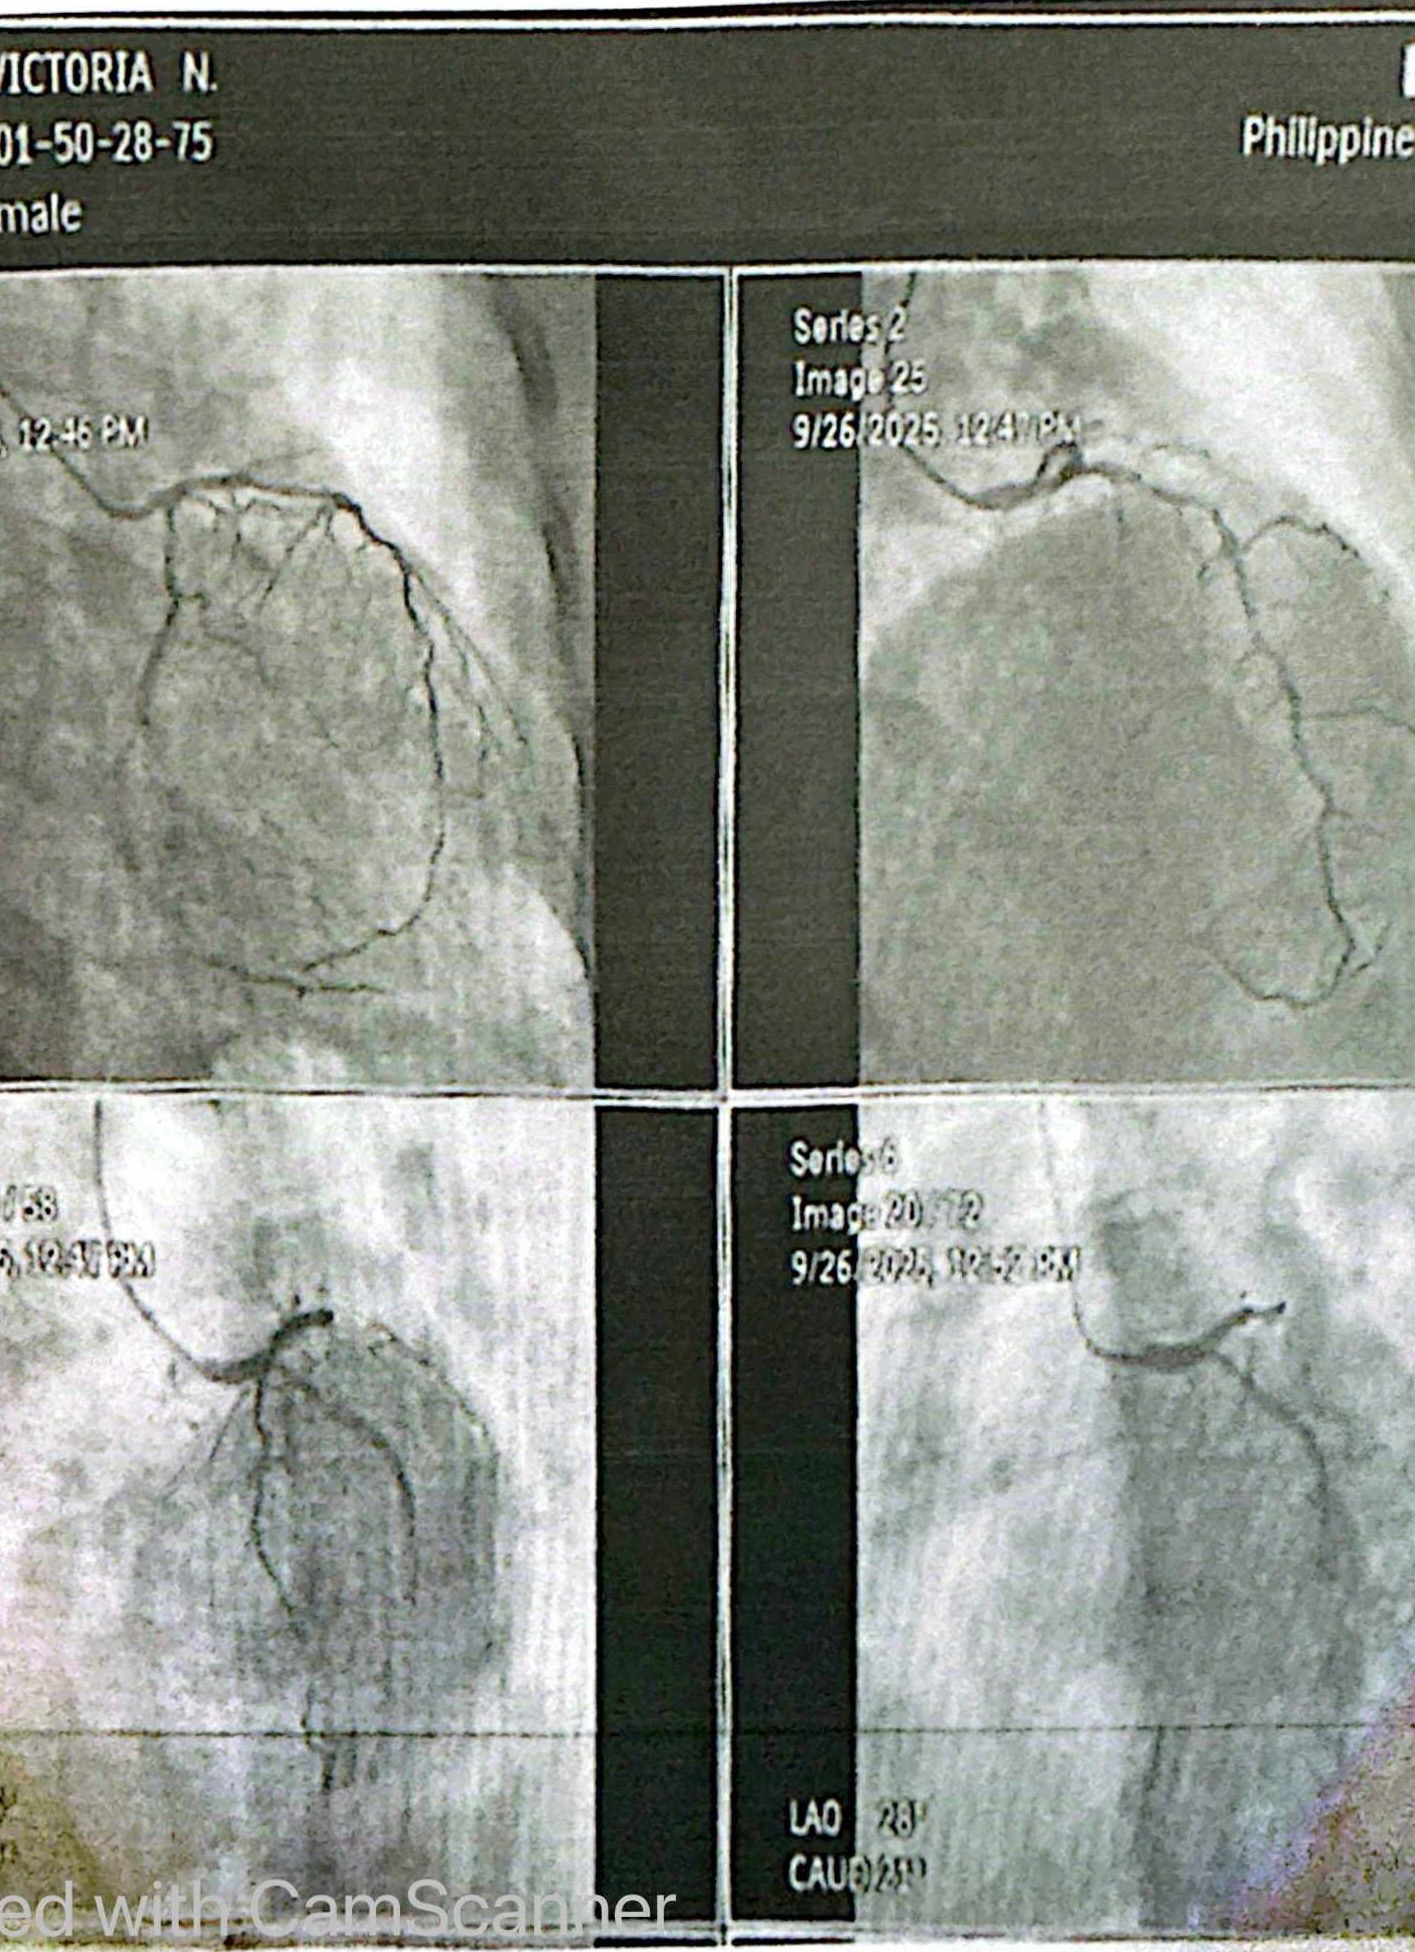

Hello everyone, my name is Aida. I'm creating this fundraiser on behalf of my sister Victoria. Her attending physician recently referred her to undergo an immediate angioplasty at the Philippine Heart Center due to alarming symptoms and test results that require urgent intervention.

In the past months, my sister had already been admitted to the hospital twice because of heart attacks with complications. Her condition has been challenging for her and heartbreaking for us to witness. The doctors had told her family that she needed this procedure as soon as possible to prevent her health from worsening.